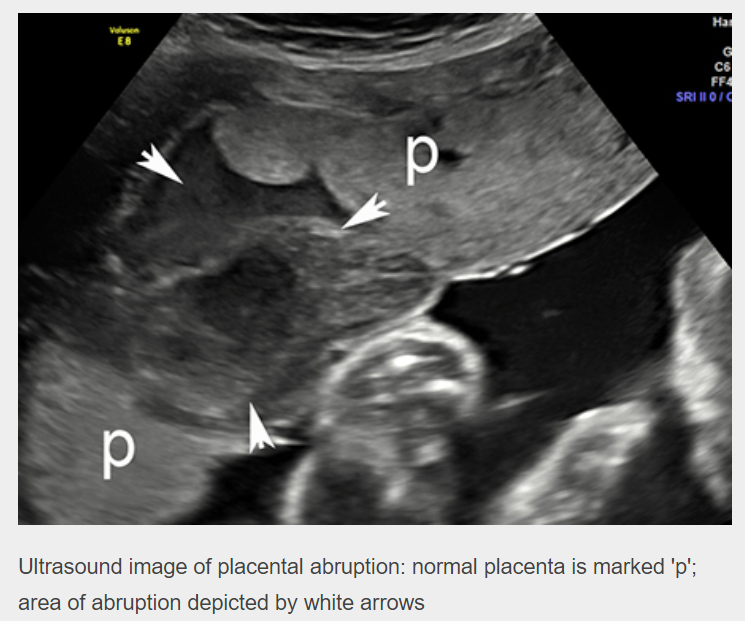

US findings in placental abruption:

Findings may include: